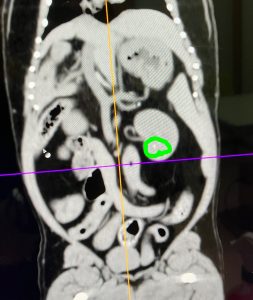

そして、CT 検査は他の病気も見つけてくれました。

緑〇は「結石」です。

両帆の腎臓に小さな石がありました。